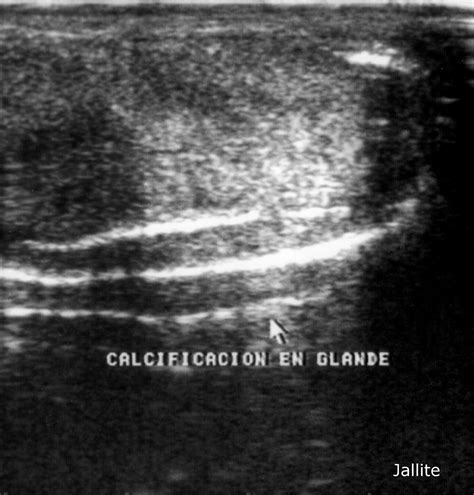

La Enfermedad de Peyronie se manifiesta cuando se desarrolla una cicatriz fibrosa, conocida como placa, dentro de la túnica albugínea, que es la capa elástica que rodea los cuerpos cavernosos del pene. Cuando esta zona pierde su elasticidad debido a la placa, el pene no puede expandirse uniformemente durante la erección, lo que resulta en una curvatura visible o un dolor persistente.

• Nódulos o placas palpables: Se pueden sentir áreas endurecidas bajo la piel del pene al tacto.